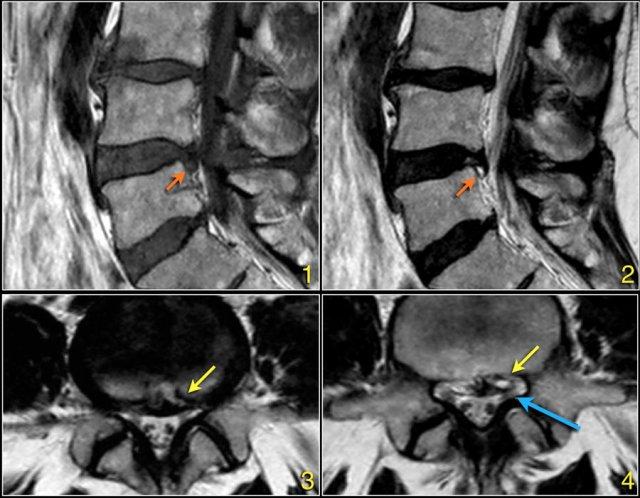

Cường độ tín hiệu của thoát vị đĩa đệm trên chuỗi xung T1W thường ở mức trung gian, trong khi trên chuỗi xung T2W có thể tăng tín hiệu trong trường hợp nhân nhầy thoát vị mới hoặc giảm tín hiệu trong trường hợp thoát vị cũ hơn.

Hình ảnh thoát vị tăng tín hiệu (mũi tên vàng trên ảnh cắt ngang) trượt qua vết rách vòng sợi và chèn ép rễ thần kinh L5 bên trái (mũi tên xanh dương).

Hình ảnh chuỗi xung T1W mặt phẳng đứng dọc cho thấy một cấu trúc giảm tín hiệu rất thấp tại mức L4L5 (mũi tên) và tại mức L5S1.

Tiếp tục xem các hình ảnh chuỗi xung T2W.

Trên chuỗi xung T2W, cường độ tín hiệu cũng rất thấp.

Chụp CT được thực hiện để xác định liệu đây có phải là đĩa đệm thoát vị bị vôi hóa hay một xảo ảnh nào đó.

Tiếp tục xem các hình ảnh CT.

Tín hiệu thấp cuối cùng được giải thích là do hiện tượng chân không (vacuum phenomenon) gây ra bởi khí nitơ trong đĩa đệm thoát vị tại cả mức L4L5 (mũi tên đỏ) và mức L5S1 (mũi tên xanh dương).